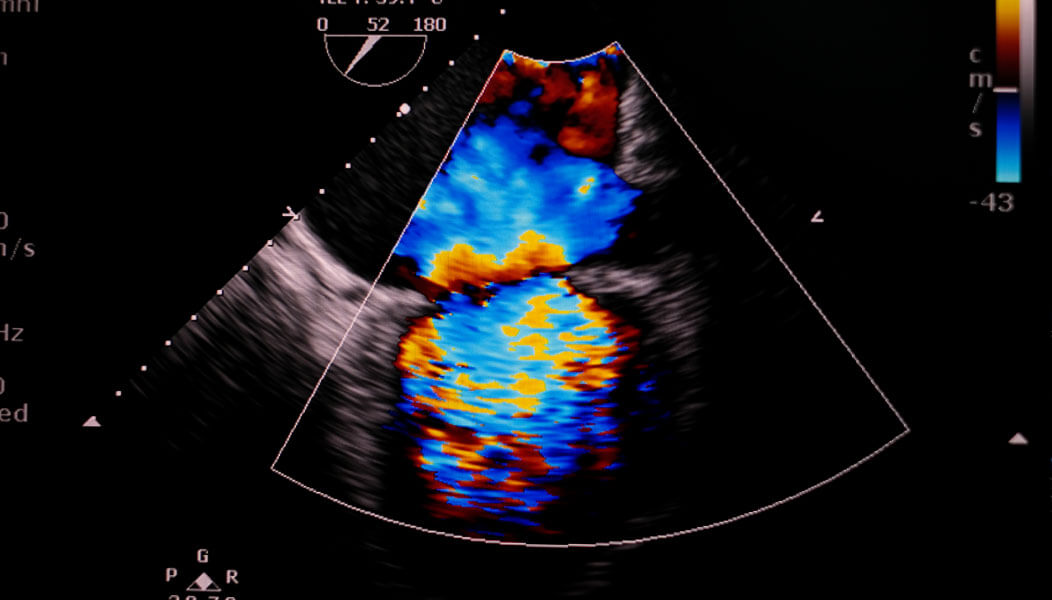

الابتكارات الطبية د. لوك بورشيل، بكالوريوس الطب والجراحة، دكتوراة د. لوك بورشيل، بكالوريوس الطب والجراحة، دكتوراة إمكانات جديدة نابعة من القلب. تطوير أساليب تشخيص مرض القلب الخلقي وعلاجه د. لوك بورشيل، بكالوريوس الطب والجراحة، دكتوراة طبيب قلب، عيادة أمراض القلب الخلقية لدى البالغين، ورئيس برنامج مسار رعاية حالات فشل القلب الخلقية لدى البالغين مدينة روتشستر، ولاية مينيسوتا عرض النص أنا الآن في مرحلة من حياتي ومسيرتي المهنية أعترف فيها بالارتباط بين القلب والعقل في عملي. أعتقد أن التدريب الطبي يعلّمكم الفصل بينهما، وألا تحتكموا إلى قلوبكم أثناء الفحوص السريرية. فأنتم تتعلمون مبكرًا كيف تصيرون أقوياء، ومن شأن هذا أن يمنحكم الحماية إلى حد ما. ولكن المشكلة هي أننا إذا فصلنا تمامًا بين القلب والعقل، فإننا نبدأ في فقدان إنسانيّتنا، وهي أهم ما يلتمسه فينا مرضانا وعائلاتهم عندما نجلس ونتحدث إليهم. لهذا نجد خطورة في الانفتاح مرة أخرى والتواصل اعتمادًا على الارتباط بين القلب والعقل. لكن نقطة القوة في ذلك أنني أمتلك صورة أفضل ليس فقط عما يفكر فيه مرضاي، بل عما يشعرون به أيضًا. ونحن نحتاج إلى أن نتفاعل على هذين المستويَين معًا إذا كنا نرغب في تقديم رعاية تلبي احتياجاتهم الحالية. عندما نفصل بين العقل والقلب، فإننا نبدأ في فقدان إنسانيتنا." يقول د. بورشيل: "أنا الآن في مرحلة من حياتي ومسيرتي المهنية أعترف فيها بالارتباط بين القلب والعقل في عملي. إن التدريب الطبي يعلّمكم الفصل بينهما، وألا تحتكموا إلى قلوبكم أثناء الفحوص السريرية. للأسف؛ عندما نفصل بين العقل والقلب، نبدأ في فقدان إنسانيّتنا." يُدرك د. بورشيل أنه عندما يتعلق الأمر بعلاج القلب، فإن الإنسانية هي ما يلتمسه مرضاه. "لقد تعلمت مبكرًا كيف أصير قويًا، وهذا يحميني بصورةٍ ما. فهناك خطورة في الانفتاح والتواصل اعتمادًا على الارتباط بين القلب والعقل. لكننا نحتاج إلى أن نتفاعل على هذين المستويَين معًا إذا كنا نرغب في تقديم رعاية تلبي احتياجات مرضانا الحالية." يعالج د. بورشيل المرضى المصابين منذ ولادتهم بمرض القلب الخلقي أو الذين وُلدوا بعيوب ذات صلة بالقلب. ويقول: "حتى لو كان المرضى قد خضعوا للجراحة أو غيرها من التدخلات، فإننا نقول إنهم قد عولجوا ولا نقول إنهم قد شُفوا، فهُم يحتاجون إلى الرعاية مدى الحياة. وفي مرحلة البلوغ، نبدأ في ملاحظة مضاعفات متأخرة؛ أهمها فشل القلب." للأسف، إن الإرشادات المتعلقة بفشل القلب مكتوبة للمصابين بفشل القلب لا للبالغين المصابين بأمراض القلب الخلقية. والأمر ذاته ينطبق على إرشادات عيادة أمراض القلب الخلقية لدى البالغين، التي لم تُكتب للمصابين بفشل القلب. يقول د. بورشيل: "نحتاج إلى استحداث أسلوب جديد تمامًا لتقديم الرعاية لليافعين الذين يكونون غالبًا في ريعان شبابهم والذين ظلّوا يتمتعون بمرونة كبيرة في التعايش مع مرض القلب الخلقي، لكنهم الآن يواجهون آخر تحدٍّ لهم؛ وهو فشل القلب." هل تحتاج إلى رعاية؟ ابحث عن اختصاصي في مواقعنا بولايات مينيسوتا وأريزونا وفلوريدا. طلب تحديد موعد طبي كونه أحد القلائل في العالم المتخصصين في كل من أمراض القلب الخلقية لدى البالغين وفشل القلب، يقود د. بورشيل الطريق نحو إنشاء تلك اللغة الجديدة. ويتعاون د. بورشيل، باعتباره رئيسًا للجمعية الدولية لأمراض القلب الخِلقية لدى البالغين، مع مجتمع أمراض القلب الخِلقية لدى البالغين وصفوة من الخبراء في صياغة برنامج مسار رعاية المصابين بفشل القلب هو الأول من نوعه في العالم الذي يصممه المصابون بأمراض القلب الخِلقية لدى البالغين ويكون موجَّهًا لهم. ويصف هذا البرنامج بأنه "تصوّر لمسار من شأنه أن يكون دليلاً إرشاديًا لمن يحتاجون إلى رعاية متخصصة لحالات فشل القلب، بحيث تُقدَّم تلك الرعاية في المكان والزمان المناسبَين، مع مراعاة الاحتياجات القلبية والعقلية والاجتماعية والعاطفية والثقافية والروحية لكل شخص." تجدر الإشارة إلى أن د. بورشيل ليس مجرد طبيب صاحب سُمعة طيبة عالميًا، بل إنه أيضًا معالج. فيقول: "إن أصول الطب ترى أن ممارستنا تجمع بين العلم والفنّ. وفي أكثر الأحوال، يتماشى مصطلح "طبيب" مع الشق العلمي. ولكننا -مع ذلك- لا بد أن نتذكر أن الطبيب كان على الدوام يُنظر إليه على أنه معالج؛ وهذا هو الشق الفنّي الذي نمارسه." لذلك، فعندما يجلس د. بورشيل مع أحد المرضى، فإن أول شيء يفعله هو الاعتراف بأن هناك خبيرين يجلسان إلى الطاولة. فهناك خبير في التعامل مع الحالة الصحية، وهناك أيضًا المريض، وهو الخبير في حياته الخاصة. يضيف: "ونحن الاثنان معًا من يمكننا الاستناد إلى نقاط القوة الحالية للوصول إلى حلول تناسب المريض الذي نحاول تقديم الرعاية له". لدى د. بورشيل قدرة فطرية على المُعالجة. فهي جزء من تاريخه. نشأ د. بورشيل في بلدة موروبنا الواقعة في جنوب أستراليا التي يعني اسمها بلُغة السكان الأصليين "المياه العميقة"، وهناك تعلّم كيف يقدّر تقاليد أسلافه، والتي من بينها طريقة فريدة للإنصات يستخدمها في علاج مرضاه. يعتمد الإنصات العميق على الربط بين القلب والعقل، إذ يشمل ما نراه وما نشعر به وما يمكننا لمسه. فهناك مسؤولية تقع على عاتقنا عندما نجلس ونستمع إلى شخص آخر." يقول مشيرًا إلى عمله مع عيادة أمراض القلب الخلقية لدى البالغين: "أبدأ أولاً بالإنصات إلى القلب، ثم أُنصت من القلب." ويشرح هذه النقطة بقوله: "الإنصات من القلب هو الاعتماد على تاريخي بصفتي أحد السكان الأصليين من خلال ما نطلق عليه الإنصات العميق. وهو أسلوب يمتد تاريخه إلى آلاف السنين. يعتمد الإنصات العميق على الربط بين القلب والعقل، إذ يشمل ما نراه وما نشعر به وما يمكننا لمسه. فهناك مسؤولية تقع على عاتقنا عندما نجلس ونستمع إلى شخص آخر." يستخدم د. بورشيل أسلوب الإنصات العميق -منطلقًا من إرث أسلافه- للبحث عن دلائل على الأمراض التي كانت لا تلاحَظ غالبًا في السابق. فيقول: "لا يمر أسبوع لا ألتقي فيه مريضًا يحكي لي قصة عن موقف شكى فيه من أعراض وقوبلت شكواه بالتجاهل، وأخبره الطبيب أن الأمر محض تصور في رأسه. وغالبًا تكون هذه القصة متكررة على مدار شهور أو سنوات، بل ومدى الحياة أحيانًا". يقول د. بورشيل إنه فور أن يشخّص حالة ما "تتبلور الأمور فجأة أمام ذلك الشخص وتأتي عليه لحظة يقول فيها لنفسه إنه ليس مجنونًا. العديد من مرضاي لديهم حالات فريدة يصعب تشخيصها. وبعد الوصول إلى تشخيص تلك الحالات، يكونون بحاجة إلى فِرق رعاية فريدة من نوعها، وأحيانًا أنواع فريدة من الجراحات". وأخيرًا يضيف: "لا يكون علاج أولئك المرضى هو مجرد الجراحة، وإنما التأكيد على أن ألم الصدر الذي كانوا يشعرون به منذ سن السابعة كان حقيقيًا، وأننا توصلنا إلى حل له." كيف يرى د. بورشيل ما سيأتي به المستقبل؟ يقول د. بورشيل: "لطالما كان التشخيص أمرًا ضروريًا في تطور الرعاية المقدمة للمصابين بأمراض خلقية في القلب. ومع أننا نستخدم التصوير بالموجات فوق الصوتية (ألتراساوند) ومخطط صدى القلب وتصوير الأوعية التاجية بالتصوير المقطعي المحوسب والتصوير بالرنين المغناطيسي، فإنه ما يزال هناك الكثير مما نجهله عما يؤدي إلى تدهور وظائف القلب. ولهذا ستكون المرحلة التالية المُضي قدمًا في استحداث أساليب جديدة للتصوير يمكنها الوصول إلى مستوى الخلية والكشف عن الآليات الخلوية التي تسهم في حدوث فشل القلب". "أعتقد أن ما جاء بي إلى هنا كان تاريخ العلاجات الرائدة والقيمة الأساسية التي تنص على وضع احتياجات المريض على رأس قائمة الأولويات". من الأمور الأخرى التي يراها د. بورشيل مثيرة للاهتمام أهمية الصوت. فيقول: "كان زملائي ينظرون الصوت باعتباره علامة حيوية خاصة بالقلب. فبناءً على مجرد صوت شخص ما، يمكن التحديد بدرجة كبيرة من الشك أنه قد أصيب بمشكلة جديدة في نظم القلب. بل يمكنك اعتبار الصوت بمثابة بصمة يمكننا تتبعها بمرور الوقت، ووسيلة يمكن استخدامها لتحديد الحالة الصحية العامة للقلب." يضيف د. بورشيل: "لم أكن أتخيّل أبدًا في سنوات نشأتي أنني قد أنال شرف العمل في مايو كلينك. "أعتقد أن ما جاء بي إلى هنا كان تاريخ العلاجات الرائدة والقيمة الأساسية التي تنص على وضع احتياجات المريض على رأس قائمة الأولويات". وتلك الاحتياجات يلبيها د. بورشيل ليس فقط عن طريق الاستماع لمرضاه، بل بالإنصات الفعّال لهم. وهي سمة انغرست فيه منذ أيام نشأته الأولى في موروبنا. ما الذي يرغب د. بورشيل في أن يتذكره الناس به بخلاف كونه أول طبيب قلب من السكان الأصليين لأستراليا؟ يجيب: "بأنني كنت شخصًا عطوفًا، لكن من المهم لي أن أوضح أن هذا العطف يعبّر فعلاً عن القوة. فالتعامل بعطف يحتاج إلى صبر، ويحتاج إلى رحمة وكرامة وقوة. لهذا فهو عطف، ولكنه عطف ممزوج بالقوة. وهذا ما أحب أن يتذكرني الناس به". د. لوك بورشيل، بكالوريوس الطب والجراحة، دكتوراة د. لوك بورشيل اختصاصي قلب وخبير مشهور على مستوى العالم متخصص في مرض القلب الخلقي لدى البالغين. ينحدر د. بورشيل من أصول أسترالية، وقد ارتحل خلال مسيرته المهنية إلى مختلف أنحاء العالم. وفي عام 2021، انتقل مع أسرته إلى ولاية مينيسوتا للانضمام إلى فريق عيادة أمراض القلب الخلقية للبالغين في مايو كلينك ليقود برنامج مسار رعاية حالات فشل القلب الخلقية لدى البالغين في مايو كلينك. تعرف على مزيد من المعلومات عن د. بورشيل مرض القلب الخلقي مرض يتضمن مشاكل في هيكل القلب موجودة منذ الولادة. وهناك عدة أنواع مختلفة لعيوب القلب الخلقية. تعرف على مزيد من المعلومات عن مرض القلب الخلقي فشل القلب يحدث فشل القلب عندما لا تضخ عضلة القلب الدم بالكفاءة المطلوبة، ما يؤدي إلى ضيق النفس وغير ذلك من الأعراض المتعلقة بأعضاء الجسم الداخلية. تعرف على مزيد من المعلومات عن فشل القلب قسم طب القلب والأوعية الدموية في مايو كلينك قسم طب القلب والأوعية الدموية في مايو كلينك من أكبر عيادات القلب وأكثرها شمولاً على مستوى العالم. تعرف على مزيد من المعلومات عن قسم طب القلب والأوعية الدموية في مايو كلينك تعرف على الأطباء المشاركين في لحظات الاكتشاف الفارقة. نشهد الآن وهُنا في مايو كلينك مجموعة من الابتكارات التي ستحطم المستحيل. تعرف على الأطباء وأفراد فِرق العمل المختصة الذين يستفيدون من كل التطورات الطبية الرائدة لتوفير فرص علاج ما كان علاجه مستحيلاً من قبل. ابقَ على تواصل معنا. سجّل اشتراكك للحصول على مقاطع فيديو ومقالات وأفكار من الأطباء والفِرق المختصة في مايو كلينك. إرسال تعرف على المزيد حول استخدام مايو كلينك للبيانات. قد ندمج معلومات بريدك الإلكتروني واستخدامك للموقع مع معلومات أخرى لدينا عنك لتوفير أكثر المعلومات ملاءمة وفائدة لك، وفهم أي المعلومات المفيدة لك. إذا كنت تتلقى الرعاية في مايو كلينك، فإن هذه البيانات قد تتضمن معلومات صحية محمية. إذا دمجنا هذه البيانات مع معلوماتك الصحية المحمية، فسنعامل كل هذه المعلومات باعتبارها معلومات صحية محمية ولن نستخدمها أو نكشف عنها إلا على النحو المنصوص عليه في إشعار ممارسات الخصوصية المعمول به لدينا. يمكنك إلغاء الاشتراك في مراسلات البريد الإلكتروني في أي وقت بالضغط على رابط إلغاء الاشتراك في البريد الإلكتروني.